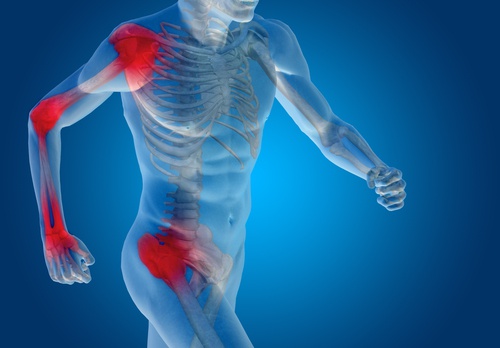

Es fundamental prestarle mucha atención a los cartílagos, ya que es un tejido que, una vez dañado, es muy difícil que pueda repararse por completo. Esto trae como consecuencia diferentes dolencias, entre ellas la artritis. Los esguinces son las habituales lesiones de este soporte. Las zonas más afectadas son:

Muñecas

Codos

Hombros

Además se pueden lesionar por quemaduras graves o por accidentes. Las heridas son muy dolorosas e incluso pueden ocasionar problemas de movilidad.

Es vital que los cartílagos se mantengan saludables, sobre todo los de las rodillas, que son los que sostienen más peso (de casi todo el cuerpo). Los síntomas más habituales de lesión o daño son: